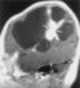

Desmoplastic infantile ganglioglioma